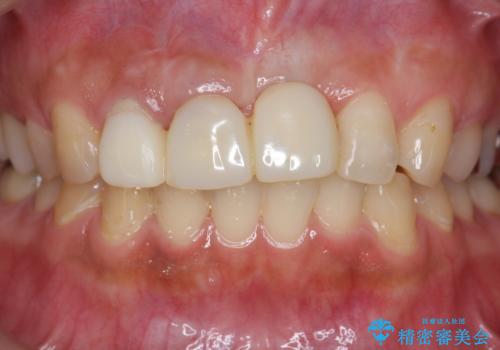

不良インプラントの除去・骨造成・歯肉移植・前歯審美セラミックブリッジ製作

- 前歯の見栄えの悪さの改善を求めて来院されました。

- 65万円(仮歯・ファイバーコア・ジルコニアクラウン・インプラント除去・骨造成・歯肉移植)費用は治療当時の料金となります